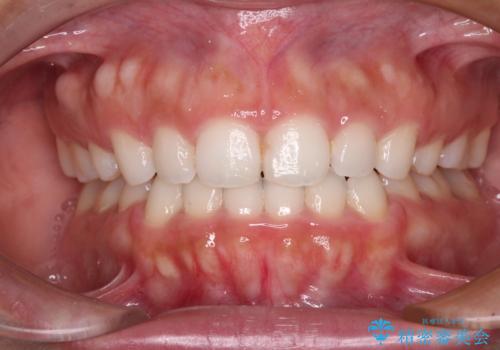

前歯の出っ歯と口の閉じにくさを抜歯矯正で改善 目立たないワイヤー矯正

出っ歯を改善した後に真っ白な歯に 矯正歯科治療と審美歯科治療